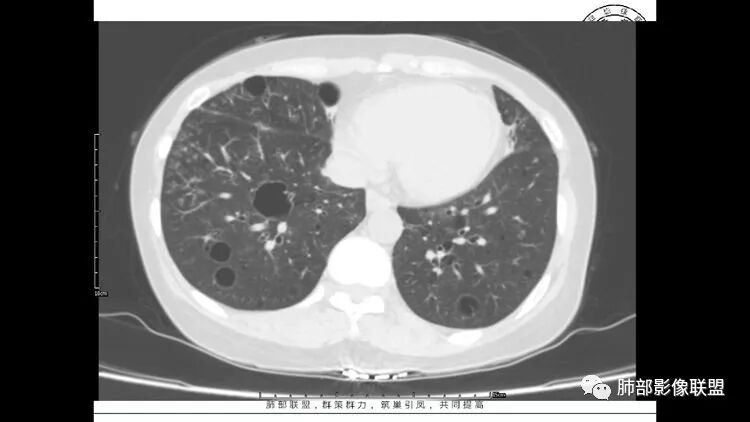

55岁女性,右眼红痛视力下降1天。既往有类风湿病史。两肺多发大小不等囊及结节,左下肺磨玻璃结节样病灶,纵隔占位。一元解释不了这么多不同病灶,二元甚至三元。纵隔恶性肿瘤并肺内转移?左下肺腺癌并肺内纵隔淋巴结转移?LIP?

wonderful

多发气囊,气囊内可见血管进入,因患者眼干伴类风湿,可能有干燥综合征,那LIP可能性大。因为不是育龄期发病,可排除LAM。患者左纵膈淋巴结肿大,且有融合趋势,结合左下肺病灶,考虑合并恶性肿瘤,淋巴瘤?鉴别结节病

1.左下肺腺癌;2.两肺弥漫性病变(多发囊腔、部分囊壁不规则,分布无特异,结节,空洞,树芽征,GGO),结合眼部情况首先考虑LIP,不典型感染(病毒或其他)待排。